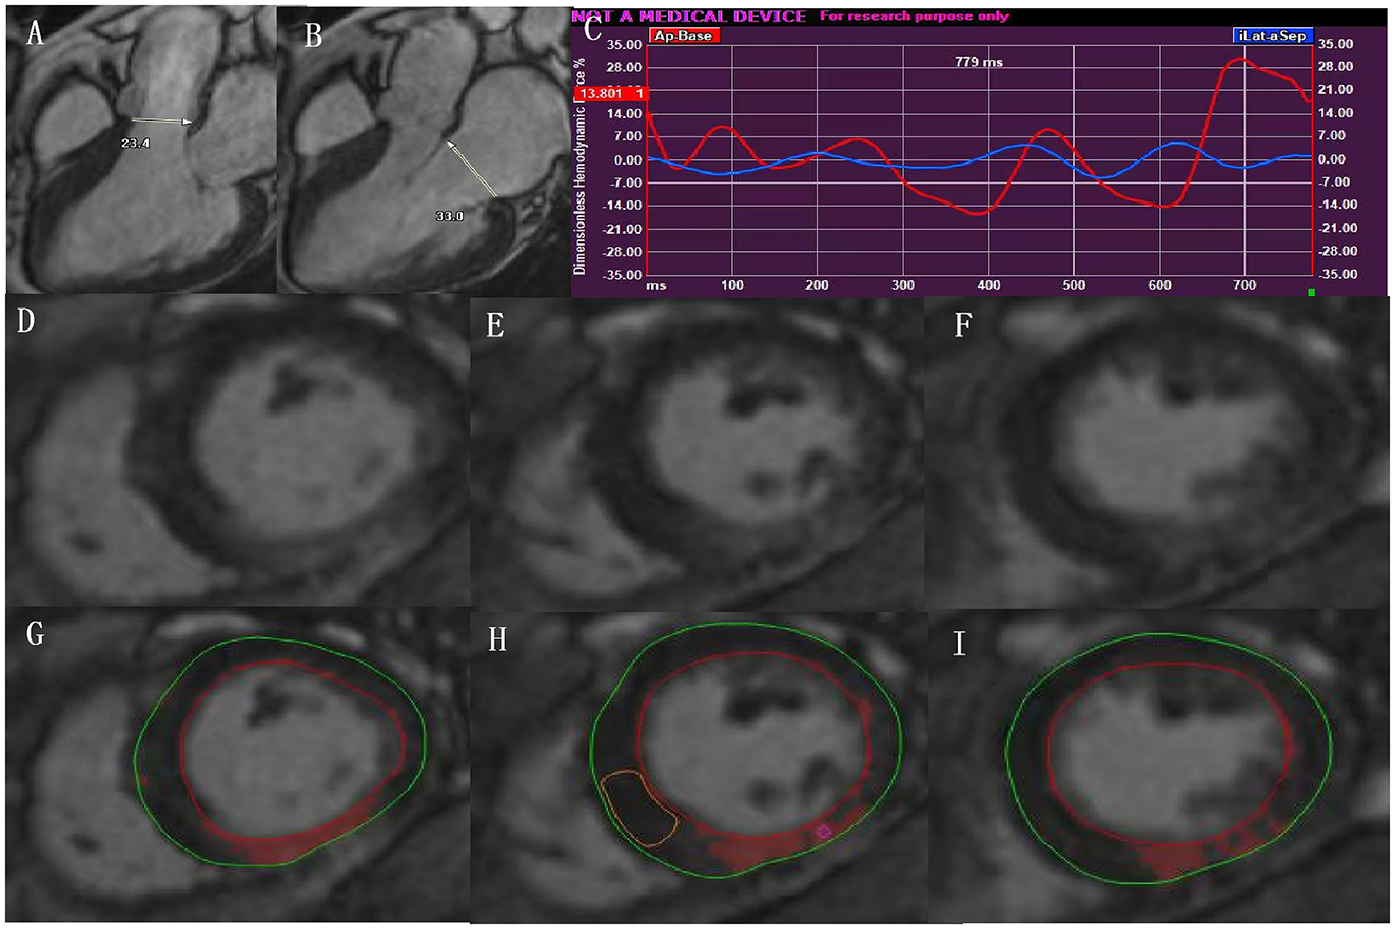

In the context of the endocardial border tracking used for LVGLS strain calculation, the maximum diameters of the aortic valve in the end-systole phase and the maximum diameters of the mitral valve in the end-diastolic phase were measured in the 3-chamber view. Then, the values of HDFs can be derived by the measured maximum diameter of aortic valve and mitral valve using the mathe-matical model integrated into the dedicated Medis software (13) (Figures 2A,B), with corresponding HDF curves (Figure 2C).

Figure 2

In the context of the endocardial border tracking used for LVGLS calculation, HDF can be acquired by measurements of the aortic and mitral diameter in the LV 3-chamber view (A,B), and with corresponding HDF curves (C); representative contours of LV LGE images from basal-apical segments in a patient with type 2 diabetes (D–F). The same images showing quantification of LGE using the 5SD thresholding method (G–I). LVGLS, left ventricular global longitudinal strain; HDF, hemodynamic forces; LGE, late gadolinium enhancement.

The diameters of the aortic and mitral valves were assessed in the 3-chamber view.

For the quantification of the extent of LGE, we imported the whole LV short-axis slices of the LGE images into the software (Figures 2D-F), and manually delineated the LV endocardial and epicardial contours. The areas of delayed myocardial enhancement was defined as a signal intensity threshold of >5 standard deviation (SD) above the mean signal intensity of the normal myocardium (14) (Figures 2G–I).